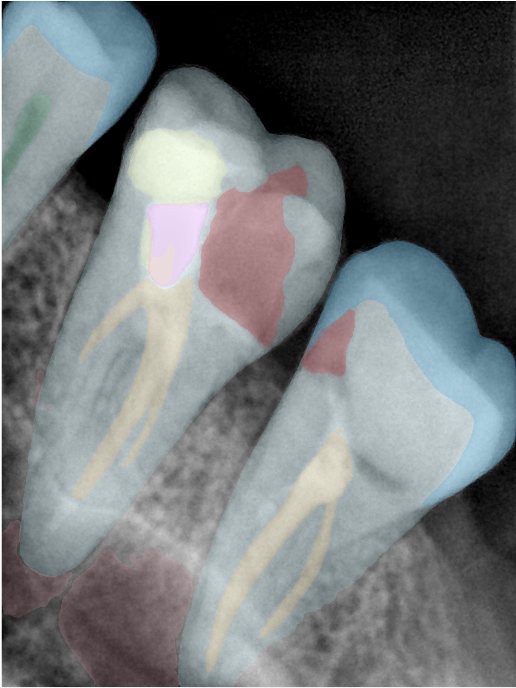

第二版算法问题测试

| 第一版 | 第二版 | 是否解决 | |

|---|---|---|---|

![]() | ![]() ![]() 边角识别有问题 龋齿识别不全 牙髓识别不全 | ![]() | 解决 |

![]() | ![]() 边角识别有问题 识别信息有误 自查(牙冠识别不全) | ![]() | 解决 |

![]() | ![]() ![]() 边角识别有误 大范围填充识别遗漏 | ![]() | 解决 |

![]() | ![]() 识别信息不全 | ![]() | 解决 |

![]() | ![]() ![]() 边角问题 牙胶识别不全 牙冠识别不全 | ![]() | 解决 |

![]() 换图片 | ![]() | ![]() 牙冠部分稍微白了一些就识别成小范围修补,部分判断异常 | 部分解决,修复类略敏感,牙冠部分稍微白了一些就识别成小范围修补,部分判断异常。 |

![]() | ![]() ![]() 牙冠识别不全 牙髓不全 根尖炎龋齿识别有误 | ![]() | 解决 |

![]() | ![]() | ![]() | 解决 |

![]() 换图片 | ![]() | ![]() | 解决 |

![]() | ![]() 牙冠识别有误 | ![]() | 解决 |

![]() 换图片 | ![]() ![]() 边角识别有误 | ![]() 修复类敏感 | 部分解决,图像过白,导致修复类判断异常。 |

![]() 换图片 | ![]() 牙冠识别不全 | ![]() 修复类敏感 | 部分解决,图像过白,导致修复类判断异常 |

结论:修复类出现了不鲁棒的情况,后续需要加入轮廓的扩充数据进行增强。